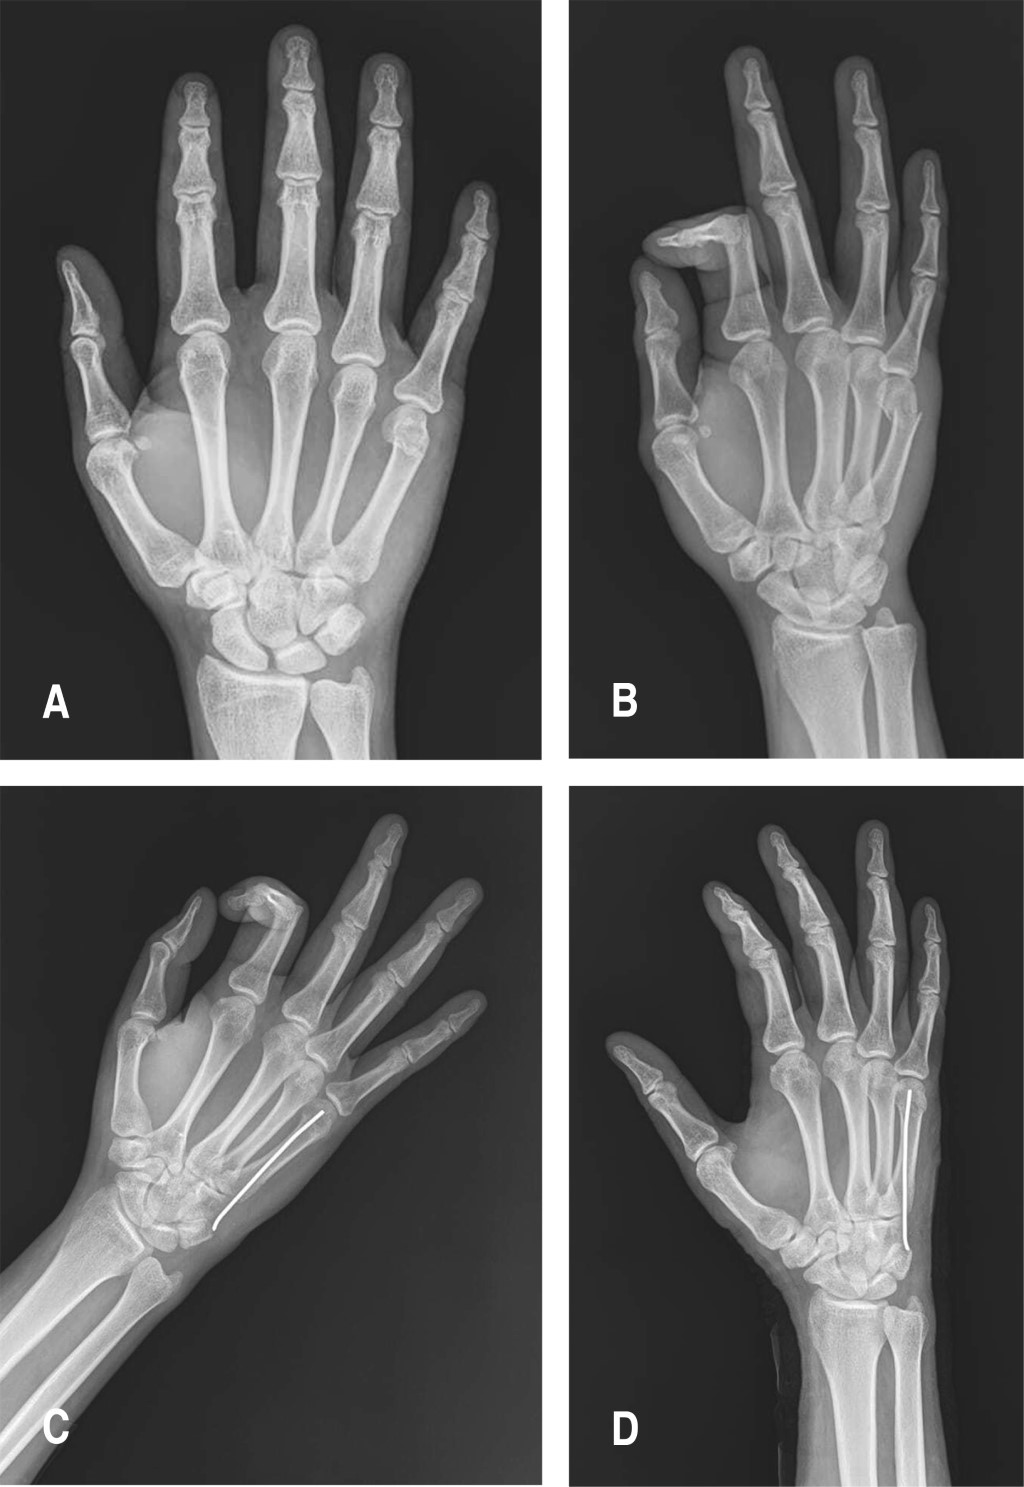

Figure 1